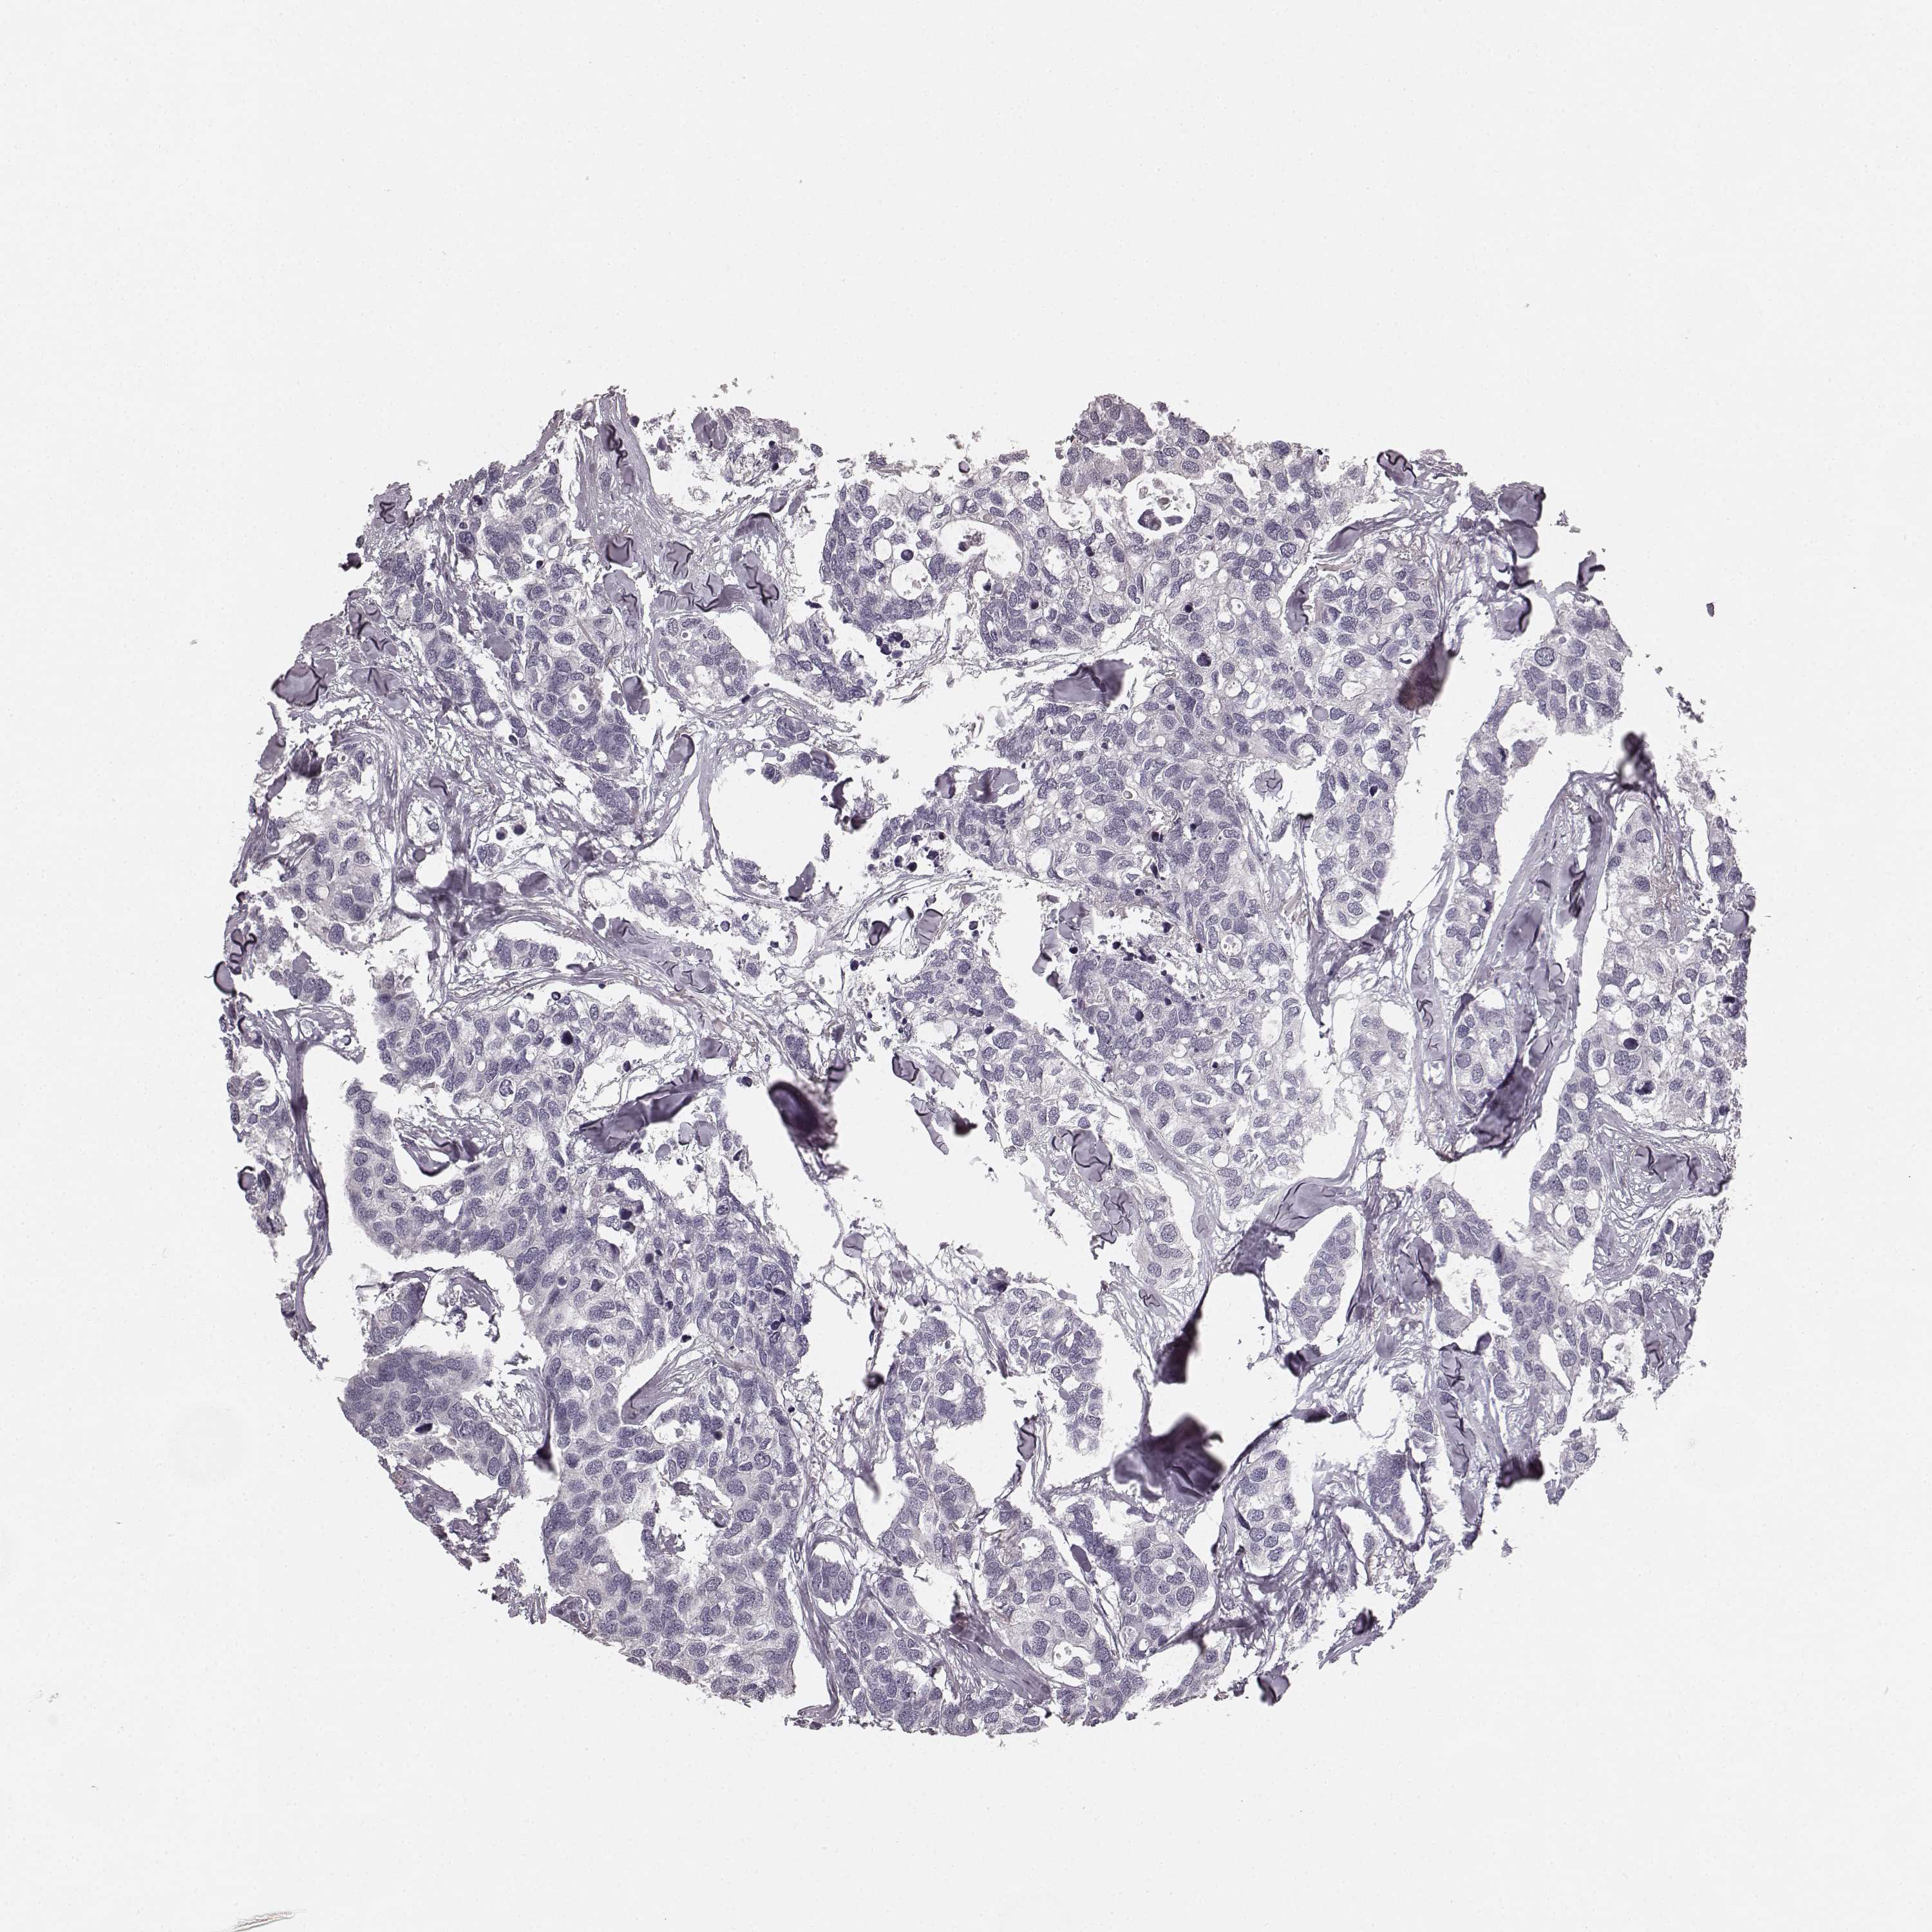

CANCER BREAST CANCER Show tissue menu

BRCA TCGA BRCA VALIDATION PROTEIN EXPRESSION